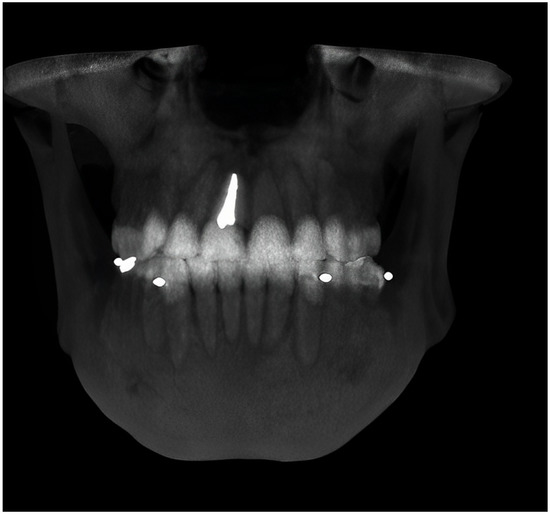

2. Materials and Methods